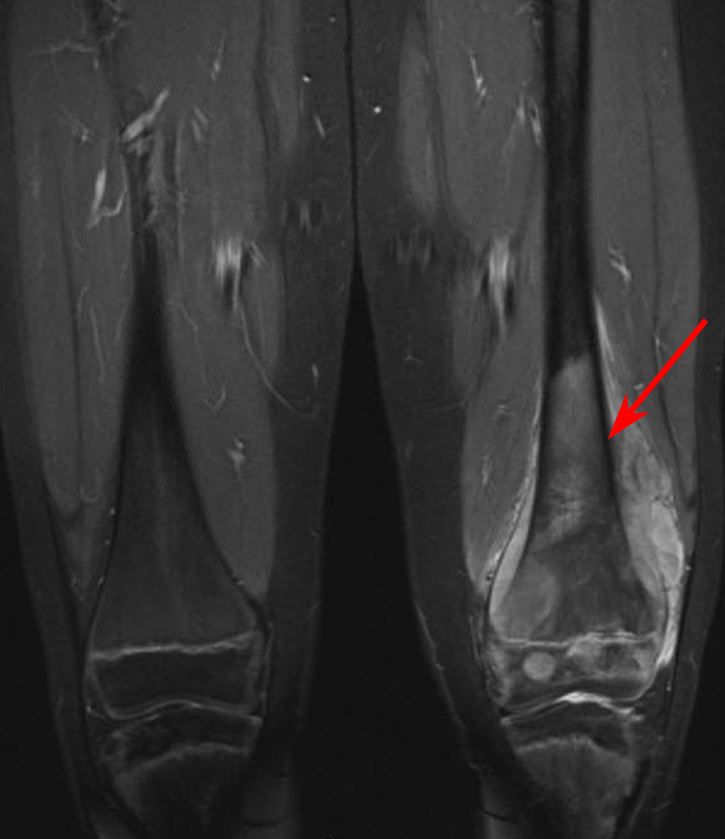

Bone cancer can begin in any bone in the body, but it most commonly affects the pelvis or the long bones in the arms and legs. Primary refers to cancer that starts in the bone versus spreading (metastasizing) into the bone from somewhere. Whether primary or metastatic, cancer in the bones may present with symptoms such as increasing pain, swelling and/or a more sudden intense pain from a pathologic fracture —a fracture that occurs in a bone that has been weakened by the presence of tumor. Foot or toe cancer (digital and soft tissue cancer), which can include squamous cell carcinoma, melanoma, osteosarcoma, mast cell tumor, and malignant soft tissue sarcoma is common in dogs. In fact, noncancerous bone tumors are much more common than cancerous ones.

Bone Pain Causes Cancer Symptoms And Treatment from post.medicalnewstoday.com It can look like a: Foot or toe cancer (digital and soft tissue cancer), which can include squamous cell carcinoma, melanoma, osteosarcoma, mast cell tumor, and malignant soft tissue sarcoma is common in dogs. Squamous cell carcinoma is the most common form of cancer on the skin of the feet. Bone cancer begins in the bone instead of developing due to cancer cells spreading from other parts of the body. Sometimes, people with bone sarcoma do not have any of these changes. Your foot has typically thin soft tissue layer and gets continuous exposure to the outside environment. A benign bone tumor of the foot will manifest as a lump, with or without pain, whereas bone cancer is most often accompanied by pain at the location of the tumor. If the cancer develops in the legs, as it does in most cases, the usual course of treatment is amputation.

Aside from looking like a changing mole, a melanoma on the foot can appear as a: For instance, lung cancer that spreads to the bone is made of lung cancer cells. A type of bone cancer called osteosarcoma is the most common type of primary bone cancer in dogs, accounting for over 95% of all bone tumors. Early on, the pain may only occur at night, or when you are active. The scc does not retain its appearance as a solid mass. Jaw cancer results in pain in the area with difficulty in opening the mouth. Bone pain can cause a dull or deep ache in a bone or bone region (e.g., back, pelvis, legs, ribs, arms). Foot or toe cancer (digital and soft tissue cancer), which can include squamous cell carcinoma, melanoma, osteosarcoma, mast cell tumor, and malignant soft tissue sarcoma is common in dogs. People with bone sarcoma may experience the following symptoms or signs. However, you should still check your symptoms and talk to your doctor, as symptoms like bone pain, fractures, swelling, and fatigue can indicate cancer or another issue that needs to be treated. In fact, noncancerous bone tumors are much more common than cancerous ones. Malignant cells in the jaw tend to spread quickly to adjacent organs. Bone cancer is a fairly rare disease, so if you've developed bone pain, don't jump to conclusions.

The bone may look ragged, or it may appear to have a hole in it. Aside from looking like a changing mole, a melanoma on the foot can appear as a: Leg pain due to bone cancer may worsen during nighttime. Sometimes, people with bone sarcoma do not have any of these changes. A benign bone tumor of the foot will manifest as a lump, with or without pain, whereas bone cancer is most often accompanied by pain at the location of the tumor.

Life At Dearborn Congregational Lung Cancer Bone Cancer And Neuropathy Oh My from 64.media.tumblr.com Cancer that arises from the jaw bone is termed primary jaw cancer. Lumps, swellings, fractures, joint tenderness and pain are some common symptoms of bone cancer in ankle and foot. Aside from looking like a changing mole, a melanoma on the foot can appear as a: Sometimes, people with bone sarcoma do not have any of these changes. Bone cancer can weaken the bone it's in, but most of the time the bones do not fracture (break). It is important that all these symptoms are identified at an early stage so, to. For instance, lung cancer that spreads to the bone is made of lung cancer cells. This article will look at what bone metastasis is and its treatment options.

When a bone tumor grows, it presses on healthy bone tissue and can destroy it, which causes the following symptoms: Bone cancer can begin in any bone in the body, but it most commonly affects the pelvis or the long bones in the arms and legs. However, malignant cells can also spread to the jaw from other cancers in the neck and head, termed as secondary jaw cancer. Bone cancer is a fairly rare disease, so if you've developed bone pain, don't jump to conclusions. It may resemble a plantar's wart or a foot ulcer, and it may feel scaly. Rarely, the affected bone may weaken and break on its own. A tumor that has metastasized to bone is not made of bone cells. Leg pain due to bone cancer may worsen during nighttime. Primary bone tumors can be either benign or malignant. They work to destroy the tumor or slow down the growth of cancer cells. Aside from looking like a changing mole, a melanoma on the foot can appear as a: If the cancer develops in the legs, as it does in most cases, the usual course of treatment is amputation. However, you should still check your symptoms and talk to your doctor, as symptoms like bone pain, fractures, swelling, and fatigue can indicate cancer or another issue that needs to be treated.

Other types of bone cancer include chondrosarcoma, fibrosarcoma, and hemangiosarcoma. Bone cancer is a fairly rare disease, so if you've developed bone pain, don't jump to conclusions. Primary bone tumors are relatively rare after the fourth decade of life and less frequent as compared to secondary bone tumors. When a bone tumor grows, it presses on healthy bone tissue and can destroy it, which causes the following symptoms: There are different types of primary bone cancers, like osteosarcoma and ewing sarcoma. Malignant cells in the jaw tend to spread quickly to adjacent organs. Jaw cancer results in pain in the area with difficulty in opening the mouth. What bone metastasis looks like. Cancer in the bones of the spine can press on nerves, causing numbness and tingling or even. People with a fracture next to or through a bone tumor usually describe sudden severe pain in a bone that had been sore for a few months. For instance, lung cancer that spreads to the bone is made of lung cancer cells. If the cancer develops in the legs, as it does in most cases, the usual course of treatment is amputation. Bone tumors of the foot are rare, comprising only three to six percent of all bone tumors, and are benign in 75 to 85 percent of cases (sarcoma, 2013).